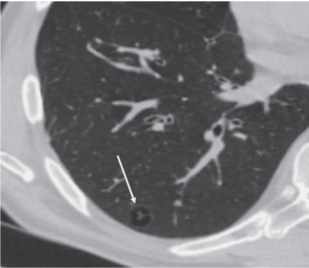

При КТ представляет собой воздушную полость с тонкими ровными ясно видимыми стенками размером более 1 см. Буллы обычно бывают множественными, так как являются одним из важных признаков легочной эмфиземы (см. Эмфизема), центрилобулярной или парасептальной, и соче

При КТ представляет собой воздушную полость с тонкими ровными ясно видимыми стенками размером более 1 см. Буллы обычно бывают множественными, так как являются одним из важных признаков легочной эмфиземы (см. Эмфизема), центрилобулярной или парасептальной, и сочетаются с другими проявлениями этой патологии.